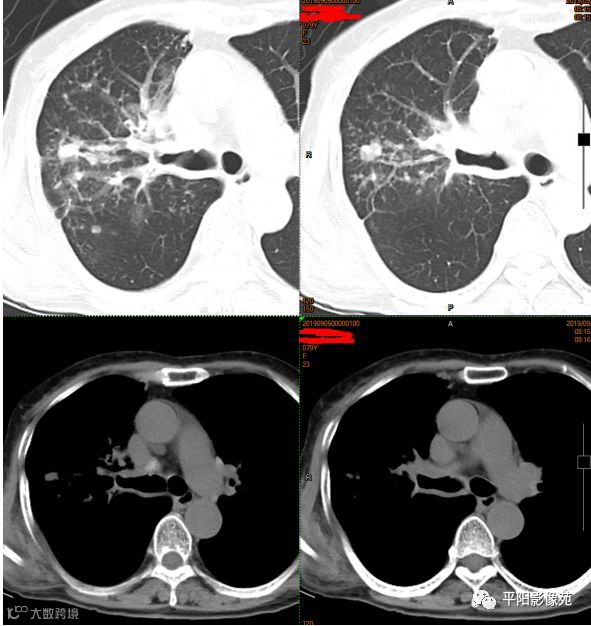

影像检查

右主支气管壁及分支壁肥厚,伴右肺上叶弥漫小叶间隔结节样增厚,不除外中央型肺癌伴癌性淋巴管炎可能。

本例影像特点,右主支气管壁肥厚,管腔狭窄不明显,管壁内缘光滑,管腔内有明显病灶堵塞,且远侧各段支气管与其他肺叶表现相同,肺内多发树叶征及实变影。

整体符合渗出、增殖、实变等特点,且病灶形态多样,局部肺间质病变反应较明显,与肺结核特征相符,而肺癌,尤其中央型肺癌,多见于鳞癌,起源于支气管壁,癌灶堆积生长,多会形成肿块且堵塞气管,引起远侧肺组织阻塞性肺气肿、肺炎、肺不张等改变,较晚期的病灶引起淋巴结转移,形成癌性淋巴管炎,但影像表现主要为肺间质不规则、结节样增厚,边缘毛糙,为网格影伴磨玻璃影,边界不清,而本例或者无此类表现,且肺组织内均为树芽征,边界清楚,与肺癌的表现不符。